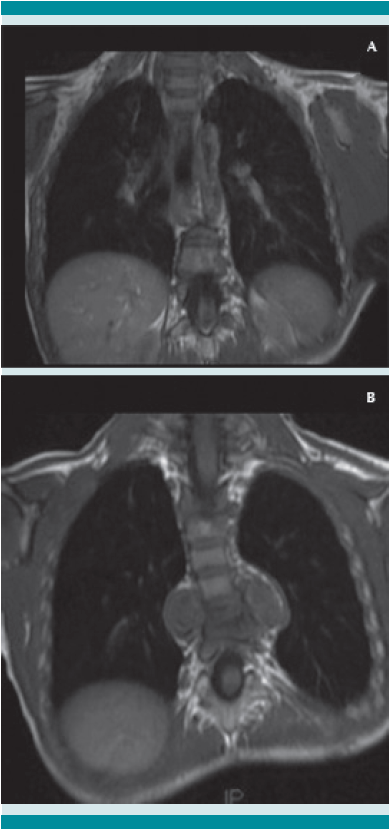

A su ingreso al Instituto Nacional de Pediatría se llevó a cabo el protocolo multidisciplinario hospitalario, que incluye la revisión por parte de los especialistas en oncología, radiología, ortopedia e infectología. En los estudios de imagen se evidenció una lesión anterior a los cuerpos vertebrales de T7-T8 de características líquidas y reforzamiento en la periferia, con destrucción de los cuerpos vertebrales de T7 y T8 a expensas del colapso vertebral que desplaza la médula espinal, con primera posibilidad diagnóstica de tipo infecciosa (espondilodiscitis). Se inició el protocolo de estudio.

La tomografía axial computada de alta resolución puede demostrar lesiones de la primoinfección o linfadenopatía, aun cuando la radiografía de tórax se reporte normal.13 La resonancia magnética se utiliza en mayor medida para la tuberculosis músculo esquelética y de tejidos blandos y, como en este caso, para diferenciar una tumoración de un granuloma en la columna vertebral.14 Otros métodos, como la gammagrafía, que con marcadores como Tecnecio 99 tiene una especificidad de 30% y con galio de 70%. El SPECT y PET tienen mejor especificidad que la tomografía o gammagrafía para discernir entre tuberculosis y lesiones cancerosas,15 con un valor predictivo negativo mayor de 90%, a diferencia de pacientes con tuberculosis pulmonar, además de mayor captación e identificación de lesiones óseas se puede utilizar como auxiliar en tuberculosis extrapulmonar. Finalmente, pueden ser de gran ayuda para determinar el grado de actividad de la enfermedad y la respuesta al tratamiento indicado.